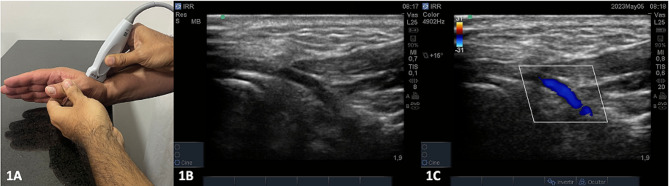

Methods: A cross-sectional study included all consecutive patients undergoing postoperative (POP) cardiac surgery with hemodynamic monitoring using PAC. Hemodynamic assessment was performed using PAC, and RRI was measured with ultrasound in the anatomical snuffbox. The Pearson correlation test was used to establish the correlation between RRI and SVRI measured using PAC. Hemodynamic behavior concerning RRI with a cutoff point of 1.1 (described to estimate under SVRI) was examined. Additionally, consistency between two evaluators was assessed for RRI using the intraclass correlation coefficient and Bland-Altman analysis.